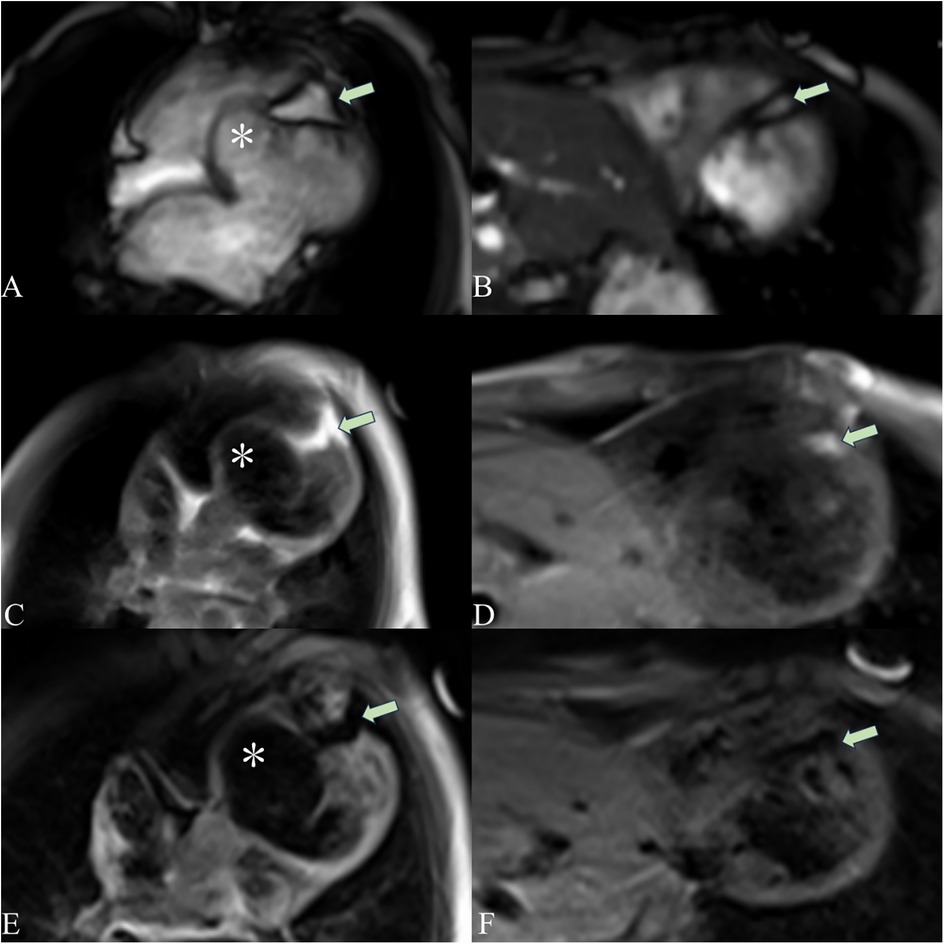

A 5-year-old boy presented with a history of cough and two fever episodes within 3 weeks. Upon admission, his vital signs were stable (T: 36.5 ℃, HR 98 bpm, RR 20 bpm). A physical examination showed the absence of wheezing, with notable cardiothoracic findings. These findings included precordial prominence, cardiomegaly on percussion (documented as 0.5-cm lateral displacement of the apical impulse from the left midclavicular line at the 5th intercostal space), and a regular cardiac rhythm without audible murmurs. His personal history (including prenatal examinations) and familial medical histories were noncontributory. A chest x-ray showed an enlarged cardiac shadow and pneumonia. Electrocardiographic findings included abnormal Q-waves, with visible Q-waves in leads II, III, aVF, and V2–V4. Additionally, ST segment changes were observed (ST segment elevation of 0.1–0.2 mV in leads V1–V4) (Figure 1A), along with QTc prolongation, left atrial heterogeneity, and double-compartment hypertrophy. Echocardiography indicated left cardiac enlargement [Left atrial volume = 28.3 ml (Z score = 4.0), LVend-diastolic diameter = 42 mm (Z score = 5.6)], a ventricular septal aneurysm in the basal and intermediate segments measuring 30 mm × 13.8 mm × 19.0 mm (Figure 2), and biventricular myocardial non-compaction with decreased LV dysfunction [ejection fraction (EF) = 40%, average E/e' = 15.4]. Computed tomographic angiography was systematically conducted for an accurate morphological assessment of the ventricular aneurysm (including topographic localization, volumetric measurement, and perianeurysmal anatomy). This technique showed left cardiac enlargement, increased trabeculation in both ventricles with a grid-like pattern, and fat density shadows within the ventricular septal myocardium (Figure 3), and a ventricular septal aneurysm. A Holter electrocardiogram showed an accelerated atrial escape rhythm (Figure 1B). Magnetic resonance imaging showed left cardiac enlargement [Left atrial volume = 34.82 ml (Z score = 4.9), LV end-diastolic volume = 76.41 ml (Z score = 4.1)], local aneurysm formation in the ventricular septum, biventricular myocardial non-compaction, and fatty infiltration in the middle and apical regions of the LV septum (Figure 4). LV systolic function was impaired (LV ejection fraction = 41.1%) and the right ventricular ejection fraction was normal (55.4%). First-pass perfusion imaging showed a perfusion defect in the ventricular septum of the mid-left ventricle and apex. Delayed enhancement imaging indicated myocardial fibrosis in the above area, which was likely secondary to myocardial ischemia.

Figure 4. Cardiac magnetic resonance imaging showing a ventricular aneurysm (*) and fatty infiltration. The cardiac magnetic resonance four-chamber view cine sequence (A), T1-weighted image (C), and T2 fat-suppression sequence (E) show a ventricular aneurysm (*) and fatty signals (arrows) in the middle and apical regions of the LV septum. The short-axis cine sequence (B), T1-weighted image (D), and T2 fat-suppression sequence (F) demonstrate fatty signals (arrows) in the middle and apical regions of the LV septum. On T1-weighted imaging, fat appears as a high-signal intensity area. The T2 fat-suppression sequence suppresses fat signals.